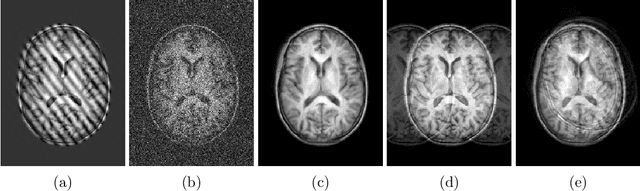

Abstract:Quality control (QC) of MR images is essential to ensure that downstream analyses such as segmentation can be performed successfully. Currently, QC is predominantly performed visually and subjectively, at significant time and operator cost. We aim to automate the process using a probabilistic network that estimates segmentation uncertainty through a heteroscedastic noise model, providing a measure of task-specific quality. By augmenting training images with k-space artefacts, we propose a novel CNN architecture to decouple sources of uncertainty related to the task and different k-space artefacts in a self-supervised manner. This enables the prediction of separate uncertainties for different types of data degradation. While the uncertainty predictions reflect the presence and severity of artefacts, the network provides more robust and generalisable segmentation predictions given the quality of the data. We show that models trained with artefact augmentation provide informative measures of uncertainty on both simulated artefacts and problematic real-world images identified by human raters, both qualitatively and quantitatively in the form of error bars on volume measurements. Relating artefact uncertainty to segmentation Dice scores, we observe that our uncertainty predictions provide a better estimate of MRI quality from the point of view of the task (gray matter segmentation) compared to commonly used metrics of quality including signal-to-noise ratio (SNR) and contrast-to-noise ratio (CNR), hence providing a real-time quality metric indicative of segmentation quality.